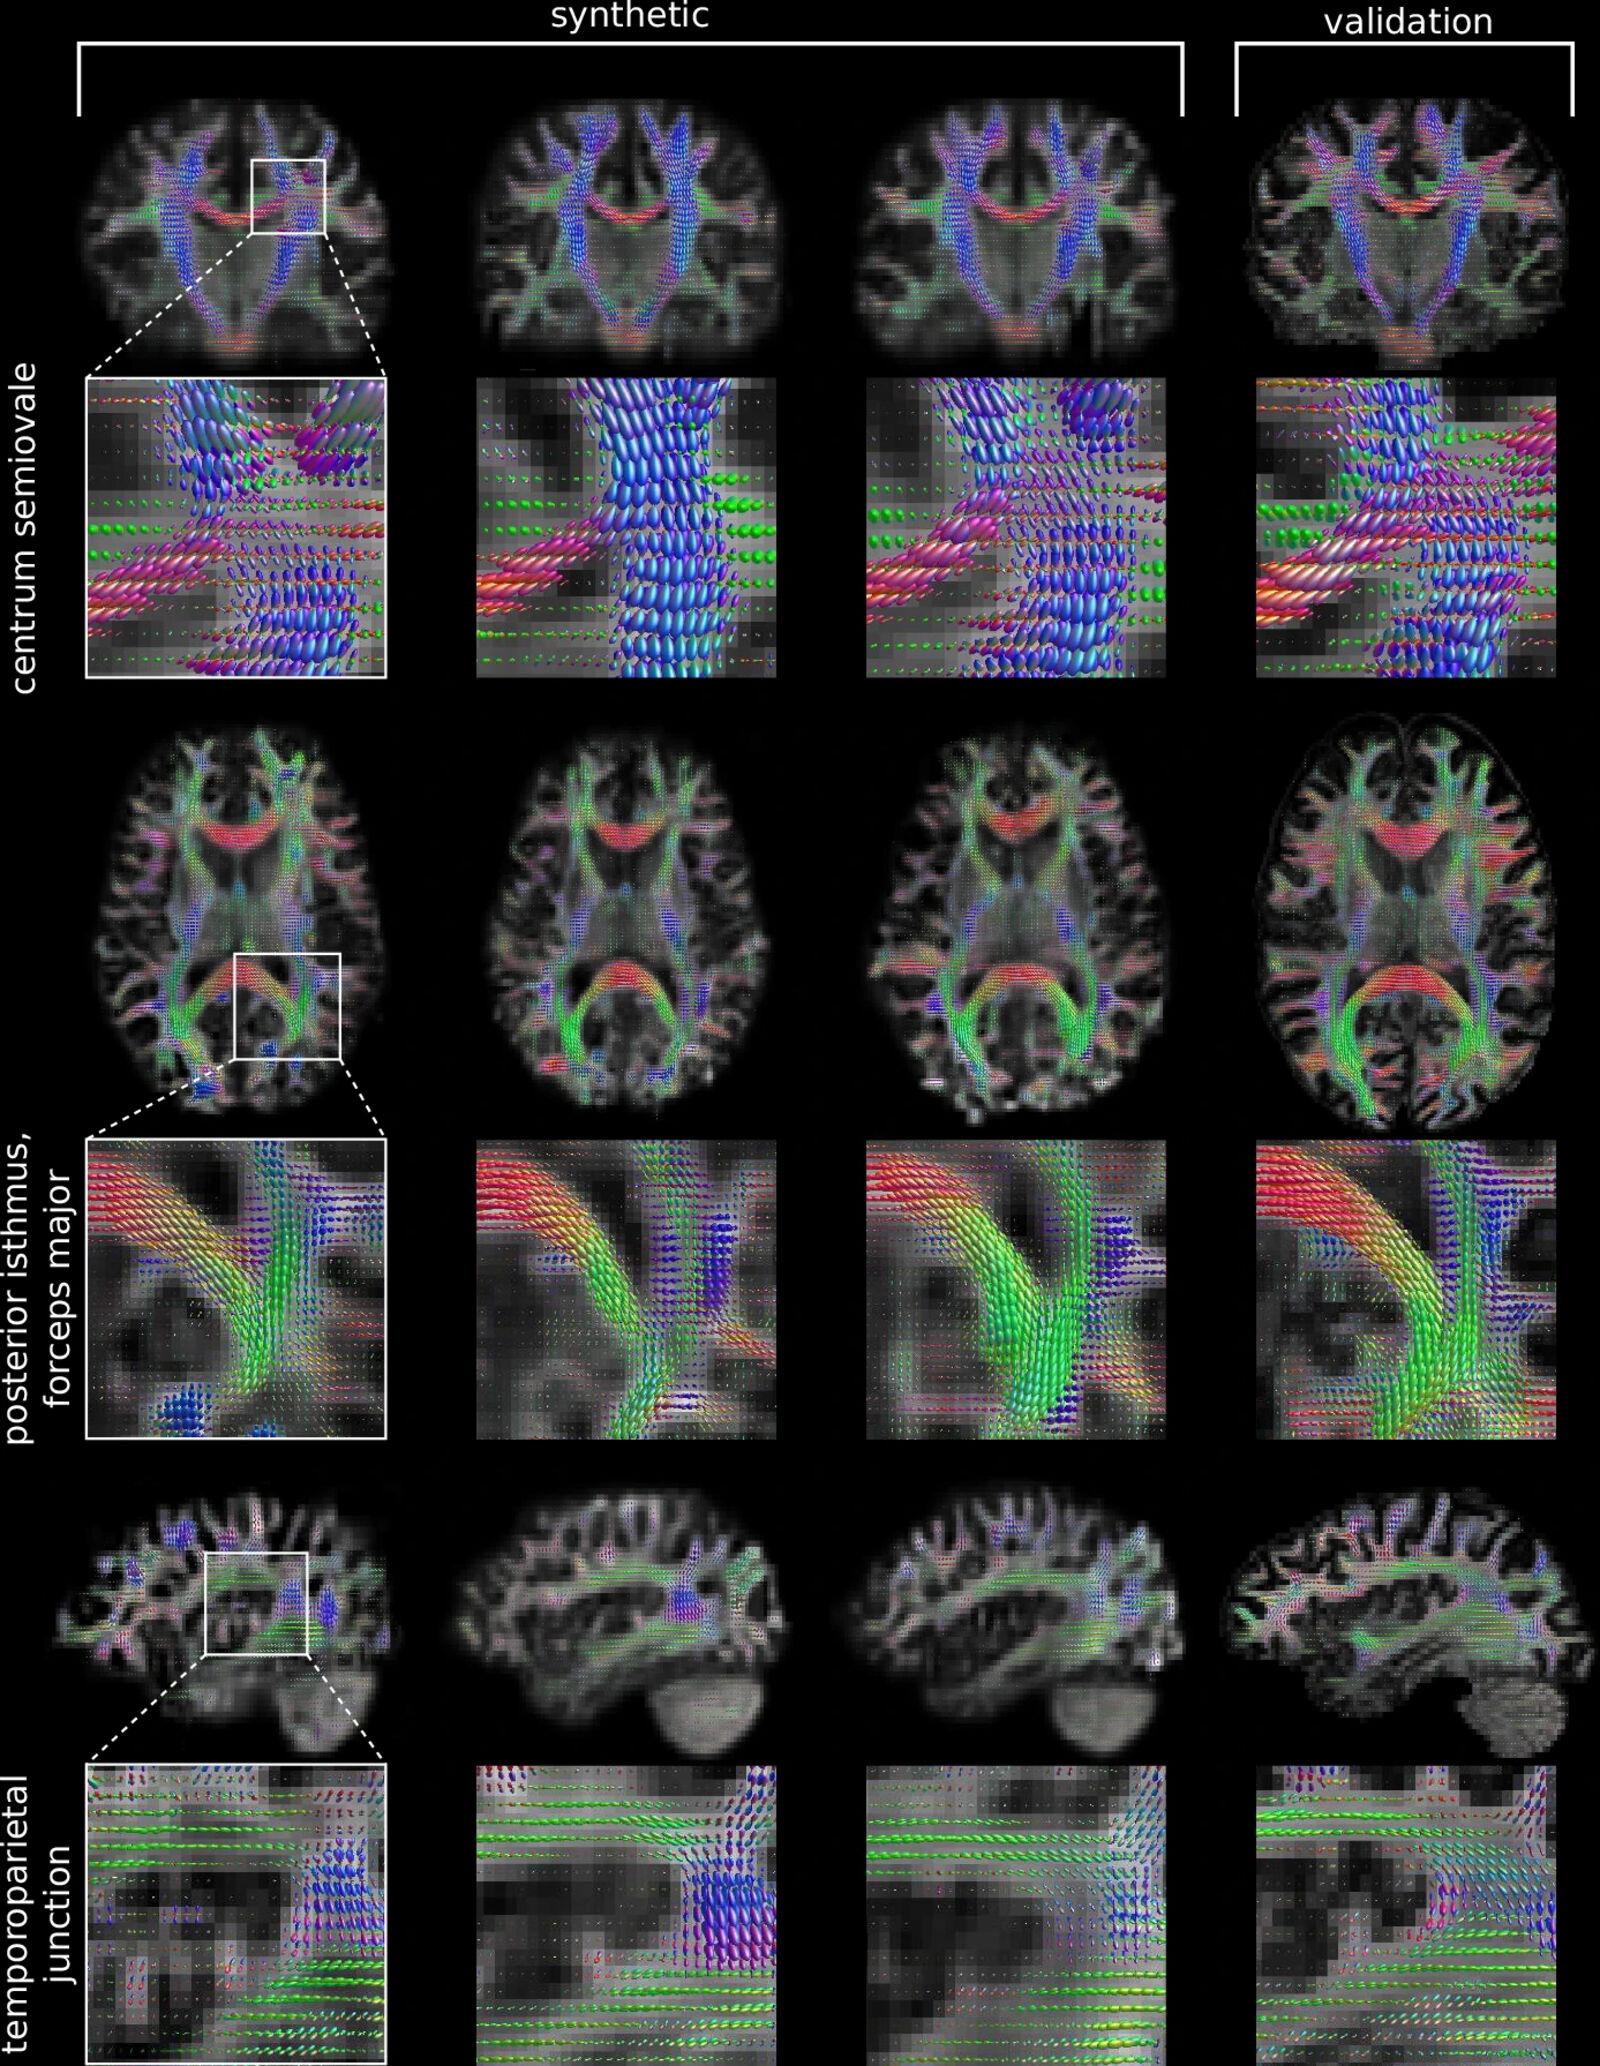

The figure shows fiber orientation distribution (FOD) data artificially generated using generative adversarial networks (GAN) compared to a validation dataset. Fig. 1 in: Vellmer, S., Aydogan, D.B., Roine, T. et al. Diffusion MRI GAN synthesizing fibre orientation distribution data using generative adversarial networks. Commun Biol 8, 512 (2025). https://doi.org/10.1038/s42003-025-07936-w.

Cutting | Brain | Publications | Yarns/Fibers The recently published article »Diffusion MRI GAN synthesizing fibre orientation distribution data using generative adversarial networks« addresses a common problem in medical research: the lack of sufficient training data, especially for rare conditions. The authors, including Cluster Members Lucius S. Fekonja and Thomas Picht, developed an innovative approach using generative adversarial networks (GANs), a machine learning framework, to create realistic synthetic fiber orientation distribution (FOD) data from diffusion MRI. FODs represent the directional diffusion patterns of water molecules in brain tissue, providing crucial information about the underlying fiber architecture. By training the machine learning model with high-quality brain scan data from the Human Connectome Project, the team demonstrated that these synthetic FODs can successfully reproduce complex microstructural properties of the brain's white matter. The team shows that this approach could significantly enhance research on rare brain disorders by providing additional training data for machine learning algorithms, ultimately supporting more accurate diagnosis and treatment planning.